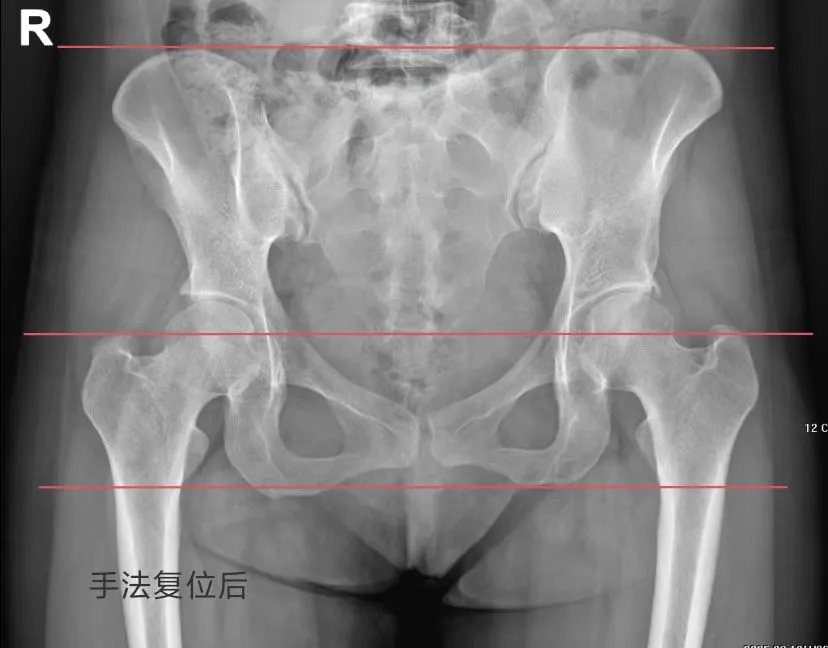

为解决李女士的问题,黄素兰医生为患者进行了骨盆手法复位,复位后,李女士感觉疼痛明显好转,可以自己起床了,走路也很顺畅了。李女士和她的丈夫向黄素兰医生表示了感谢。

(修复后骨盆)